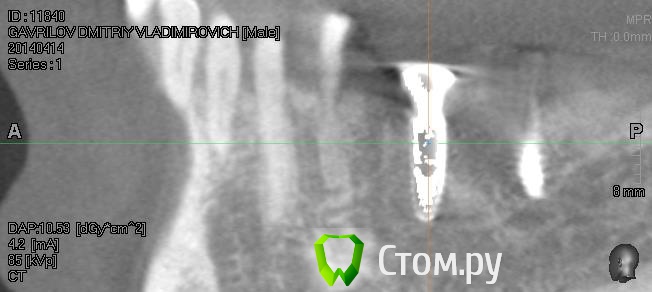

Driv Опубликовано 14 апреля, 2014 Автор Поделиться Опубликовано 14 апреля, 2014 Пойдет? Ссылка на комментарий

Bier Опубликовано 14 апреля, 2014 Поделиться Опубликовано 14 апреля, 2014 да, только надо и остальные 2 окошка тоже. наведите перекрестие на 1 и на другой имплантаты и дайте полную картинку экрана Ссылка на комментарий

Driv Опубликовано 14 апреля, 2014 Автор Поделиться Опубликовано 14 апреля, 2014 Так? Ссылка на комментарий

Bier Опубликовано 15 апреля, 2014 Поделиться Опубликовано 15 апреля, 2014 судя по этим срезам, все хорошо. 1 Ссылка на комментарий

IvanK Опубликовано 15 апреля, 2014 Поделиться Опубликовано 15 апреля, 2014 судя по этим срезам, все хорошо.Согласен Ссылка на комментарий

Driv Опубликовано 15 апреля, 2014 Автор Поделиться Опубликовано 15 апреля, 2014 СогласенКак я понимаю, вариант один, при вскрытие воспаления был поврежден нерв. Тогда вопрос, надо ли заниматься лечение поврежденного нерва, или просто ждать, когда сам восстановиться? Ссылка на комментарий

Bier Опубликовано 15 апреля, 2014 Поделиться Опубликовано 15 апреля, 2014 Да, скорее всего так, ничего не делать 1 Ссылка на комментарий